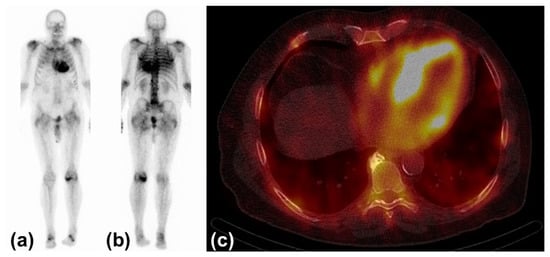

Today, three bone avid radiotracers are used to perform scintigraphy in patients with suspected CA [32]. All of them are based on the radioisotope 99mTechnetium (99mTc). 99mTc-pyrophosphate (PYP) is approved by the Food and Drug Administration (FDA) and mainly used in the United States (US). 99mTc-hydroxymethylene diphosphonate (HMDP) and 99mTc-3,3-diphosphono-1,2-propanodicarobxylicacid (DPD) are applied in Europe, but rarely or not utilized in the US. The radiotracers are injected intravenously. Whole-body planar images and chest or cardiac SPECT images are obtained two to three hours post-injection. The myocardial uptake of the tracer is then compared to the uptake of the rib cage (typically as a heart-to-bone and heart-to-contralateral ratio). It is graded from 0 to 3 according to the Perugini grading scale (0: no uptake, 1: uptake less than rib, 2: uptake equal to rib, 3: uptake greater than rib). Grades 2 and 3 are strongly suggestive for the presence of cardiac ATTR. Grade 0 is not suggestive, and Grade 1 is considered equivocal (Figure 3). Scintigraphy should always be accompanied by the performance of serum and urine immunofixation and serum-free light-chain studies. In September 2019, the American Society of Nuclear Cardiology (ASNC) and the European Association of Nuclear Medicine (EANM) published practice points regarding scintigraphy in CA.

Figure 3. Typical findings in scintigraphy and single-photon emission computed tomography: (a) Anterior view of 99Tc-hydroxymethylene diphosphonate scintigraphy with myocardial uptake Perugini Grade 3. (b) Posterior view of the same study. (c) Left and right ventricular uptake of 99mTc-hydroxymethylene diphosphonate in single-photon emission computed tomography.